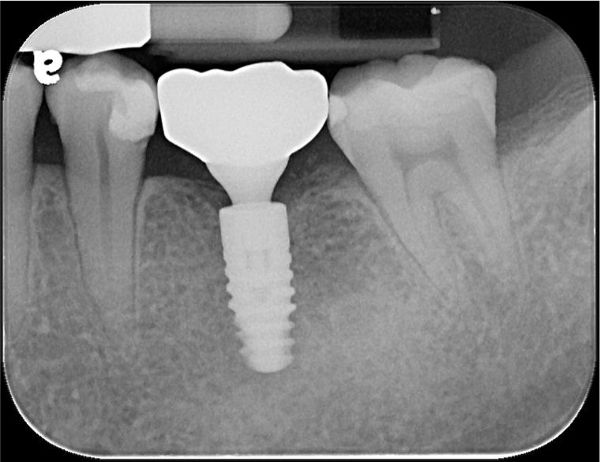

術後X光

術前、術後比較